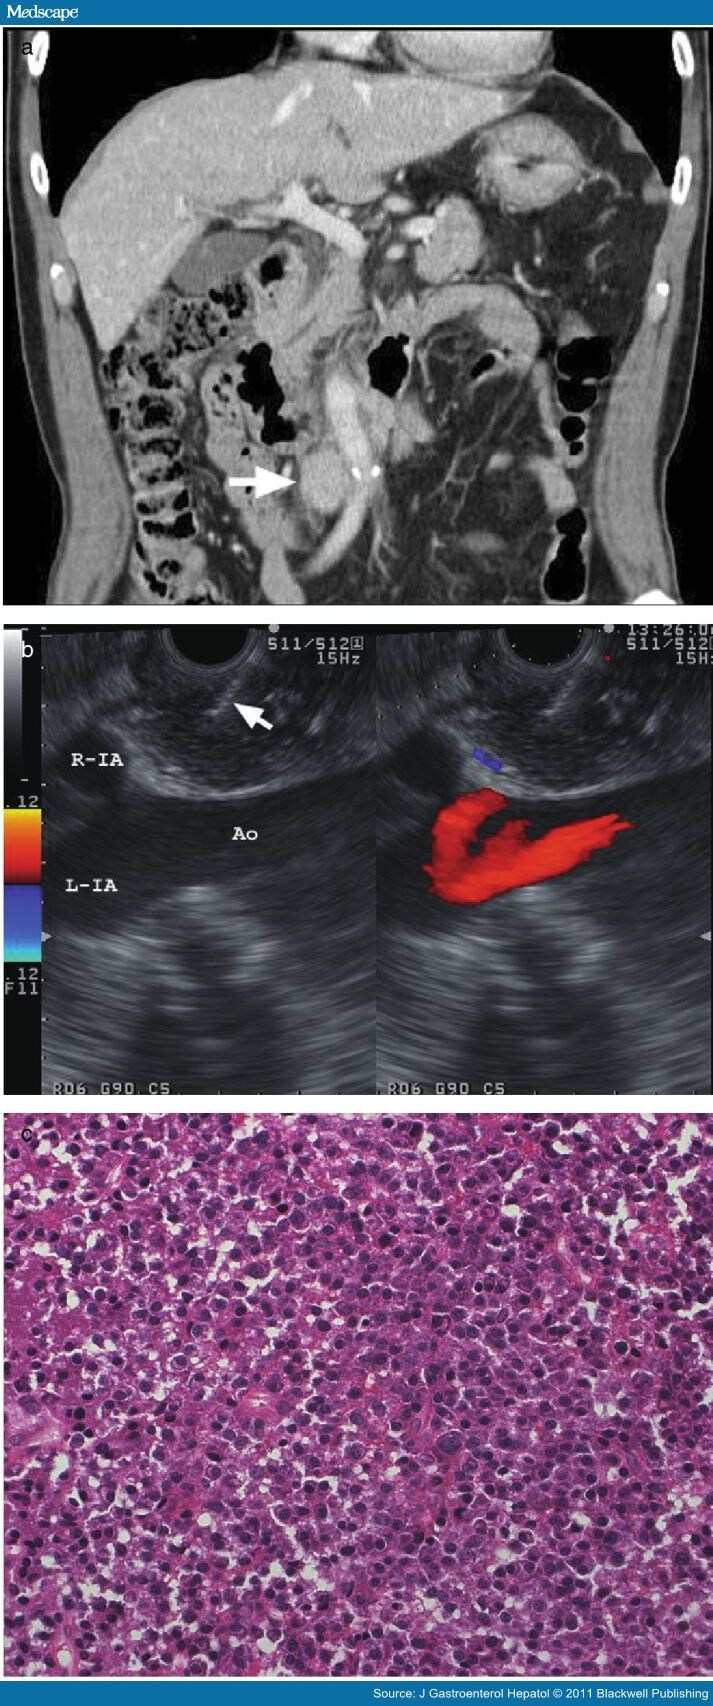

From www.medscape.com

EUSFNA of Lesions Near the Aortoiliac Bifurcation Page 2 Eus Procedure Near Me Endoscopic ultrasound (eus) is a minimally invasive procedure used to evaluate diseases in the abdomen and chest cavity. It uses a device that uses. Eus is a procedure to assess diseases of the digestive (gastrointestinal) tract and other nearby organs and tissues. An endoscopic ultrasound (eus) is a combination of two procedure, an endoscopy and an ultrasound to identify abnormalities. Eus Procedure Near Me.